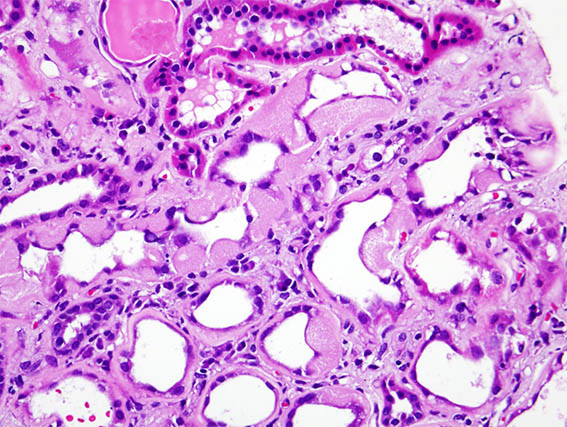

The patient is a 41-year-old woman with diabetes, who developed abrupt nephrotic syndrome, for which a kidney biopsy was performed. The biopsy shows advanced diabetic nephropathy without superimposed GN.

There is an area of tubular lesions as in the images:

Figure 1. H&E, X400. Note the tubular material.